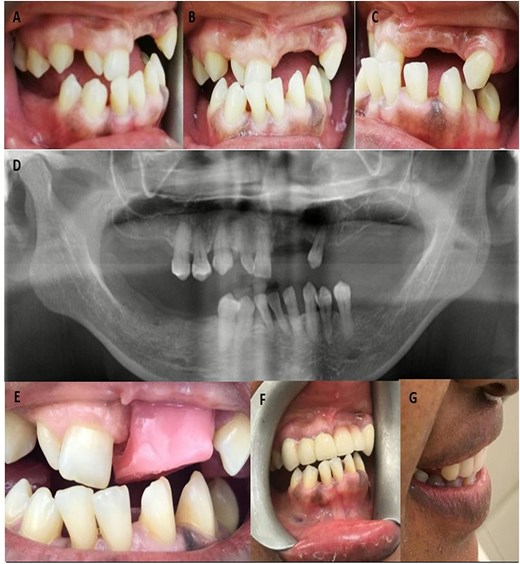

On intraoral examination, she had multiple missing teeth in both arches (#16,17, 21, 22, 24, 25, 26, 27, 36, 37, 42, 45, 46, 47) She had class III incisal relationship with traumatic deep bite anteriorly and no occlusal stops (Fig. 1A, B, and C). Oral hygiene was satisfactory. Mandibular central incisors had grade 1 mobility (Miller Index of Mobility). Remaining teeth were severely malposed. Tongue was of normal size due to wearing of dentures and she had U-shaped ridges. She had Kennedy class 1 modification 1 in maxilla and Kennedy class I in mandible.

(A) Right lateral view of bite; (B) Front view of bite; (C) Left lateral view of bite; (D) Orthopentomogram after removal of six unit bridge on maxillary anterior teeth; (E) Jaw relation record with raised bite; (F and G) Front and side view after fixed and removable denture insertion.

On examination of previous dentures, both the partial dentures lacked retention, stability, and support specifically during mastication and speech. Denture were made of acrylic with clasps on teeth#15, 23, 35, and 44. There were no mouth preparations done for previous dentures and she had a six-unit bridge on maxillary anterior teeth.

Orthopentomogram showed adequate bone available, but recession was seen around cervical regions of the teeth (Fig. 1D).

After approval from patient, the dentures were processed, polished, occlusion was adjusted and dentures were delivered (Fig. 1F and G). Oral hygiene and denture hygiene instructions were given to the patient. Other post insertion instructions about insertion or removal of denture and need for removal at night were also given. Post insertion follow up was done after a week and then one month. The patient was explained about the transitional nature of the dentures and the need for regular follow-ups.